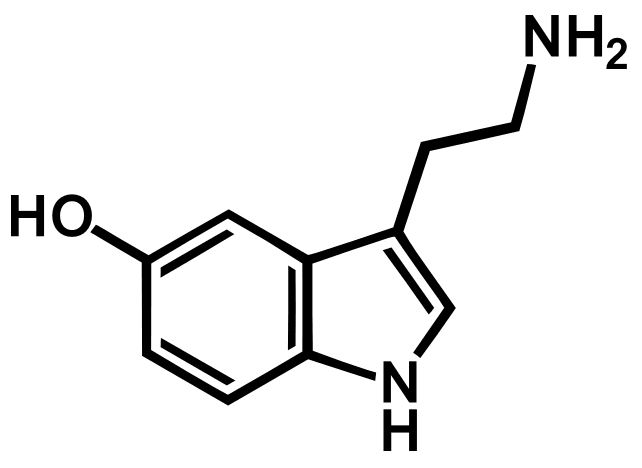

şu gördüğünüz mutluluktan sorumlu serotonin. yine 2 halkadan soldakine dikkatli bakınız.

anlayacağınız üzere serotonin triptofandan sentezlenir. zira bu indol halkasını vücudunuz yalnız triptofandan kopartarak yapabilir. yani yeterli triptofan aminoasiti alamazsanız mutlu olamazsınız. ve triptofan aminoasitince zengin besinler tüketirseniz mutlu olabilirsiniz. bunun ispatı ise aşağıdaki. evet çikolatanın sizi mutlu etme sebebi yapısında zengince triptofan aminoasiti bulundurmasıdır. bu sayede bolca indol halkası alıp bu halkadan serotonin sentezlersiniz.